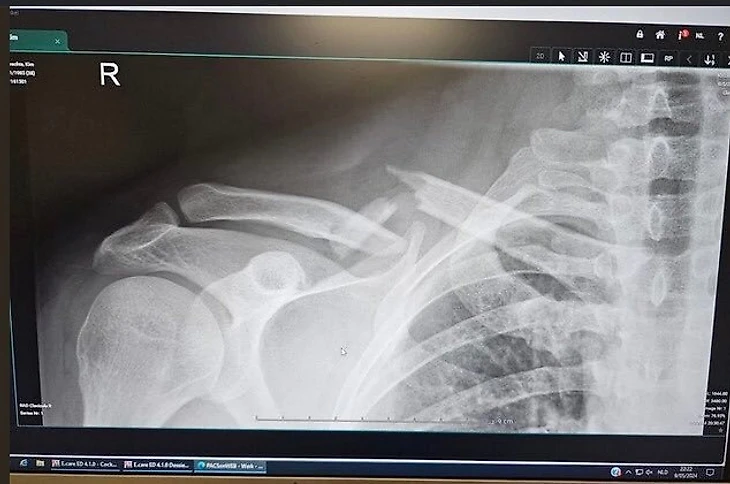

Как оказалось, атака хулиганов не прошла бесследно. Дартсмен получил двойной перелом ключицы и правой плечевой кости. Поскольку Хайбрехтс играет в дартс именно правой рукой, травма для него особенно болезненна.

Рентген Кима Хайбрехтса